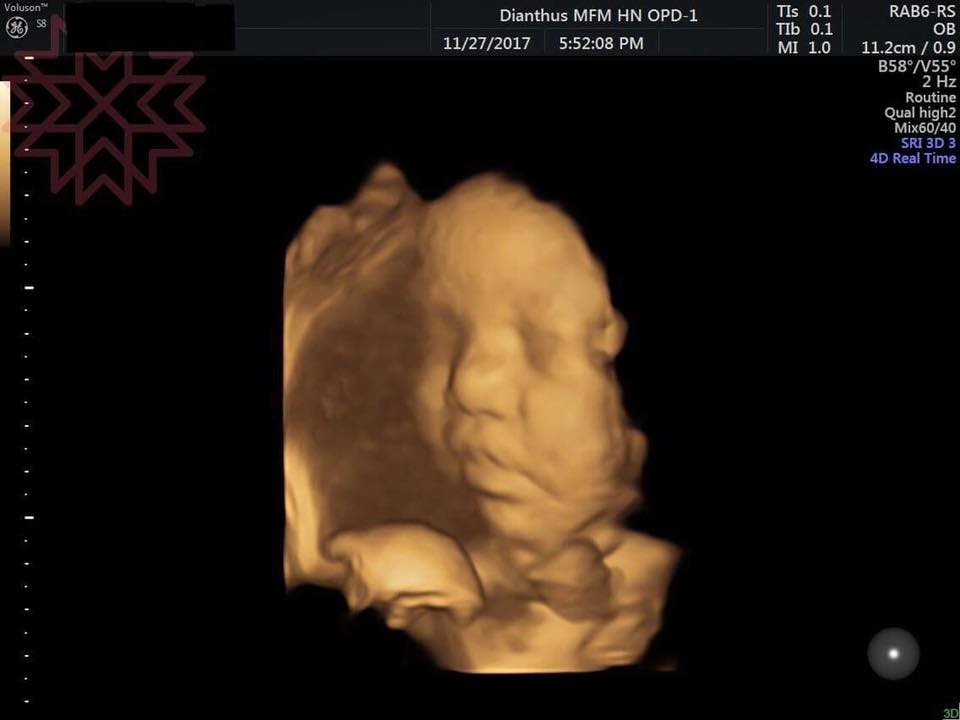

人類正常有12對肋骨,胎兒肋骨異常多在妊娠14週後用3D超音波評估最佳,尤其胎兒成趴姿時可見完整影像(如27週胎兒左第12肋缺失)。 常見單側缺失(如左第12肋),不一定影響呼吸,但若合併其他異常(如短指症),新生兒可能血氧低或需加護。